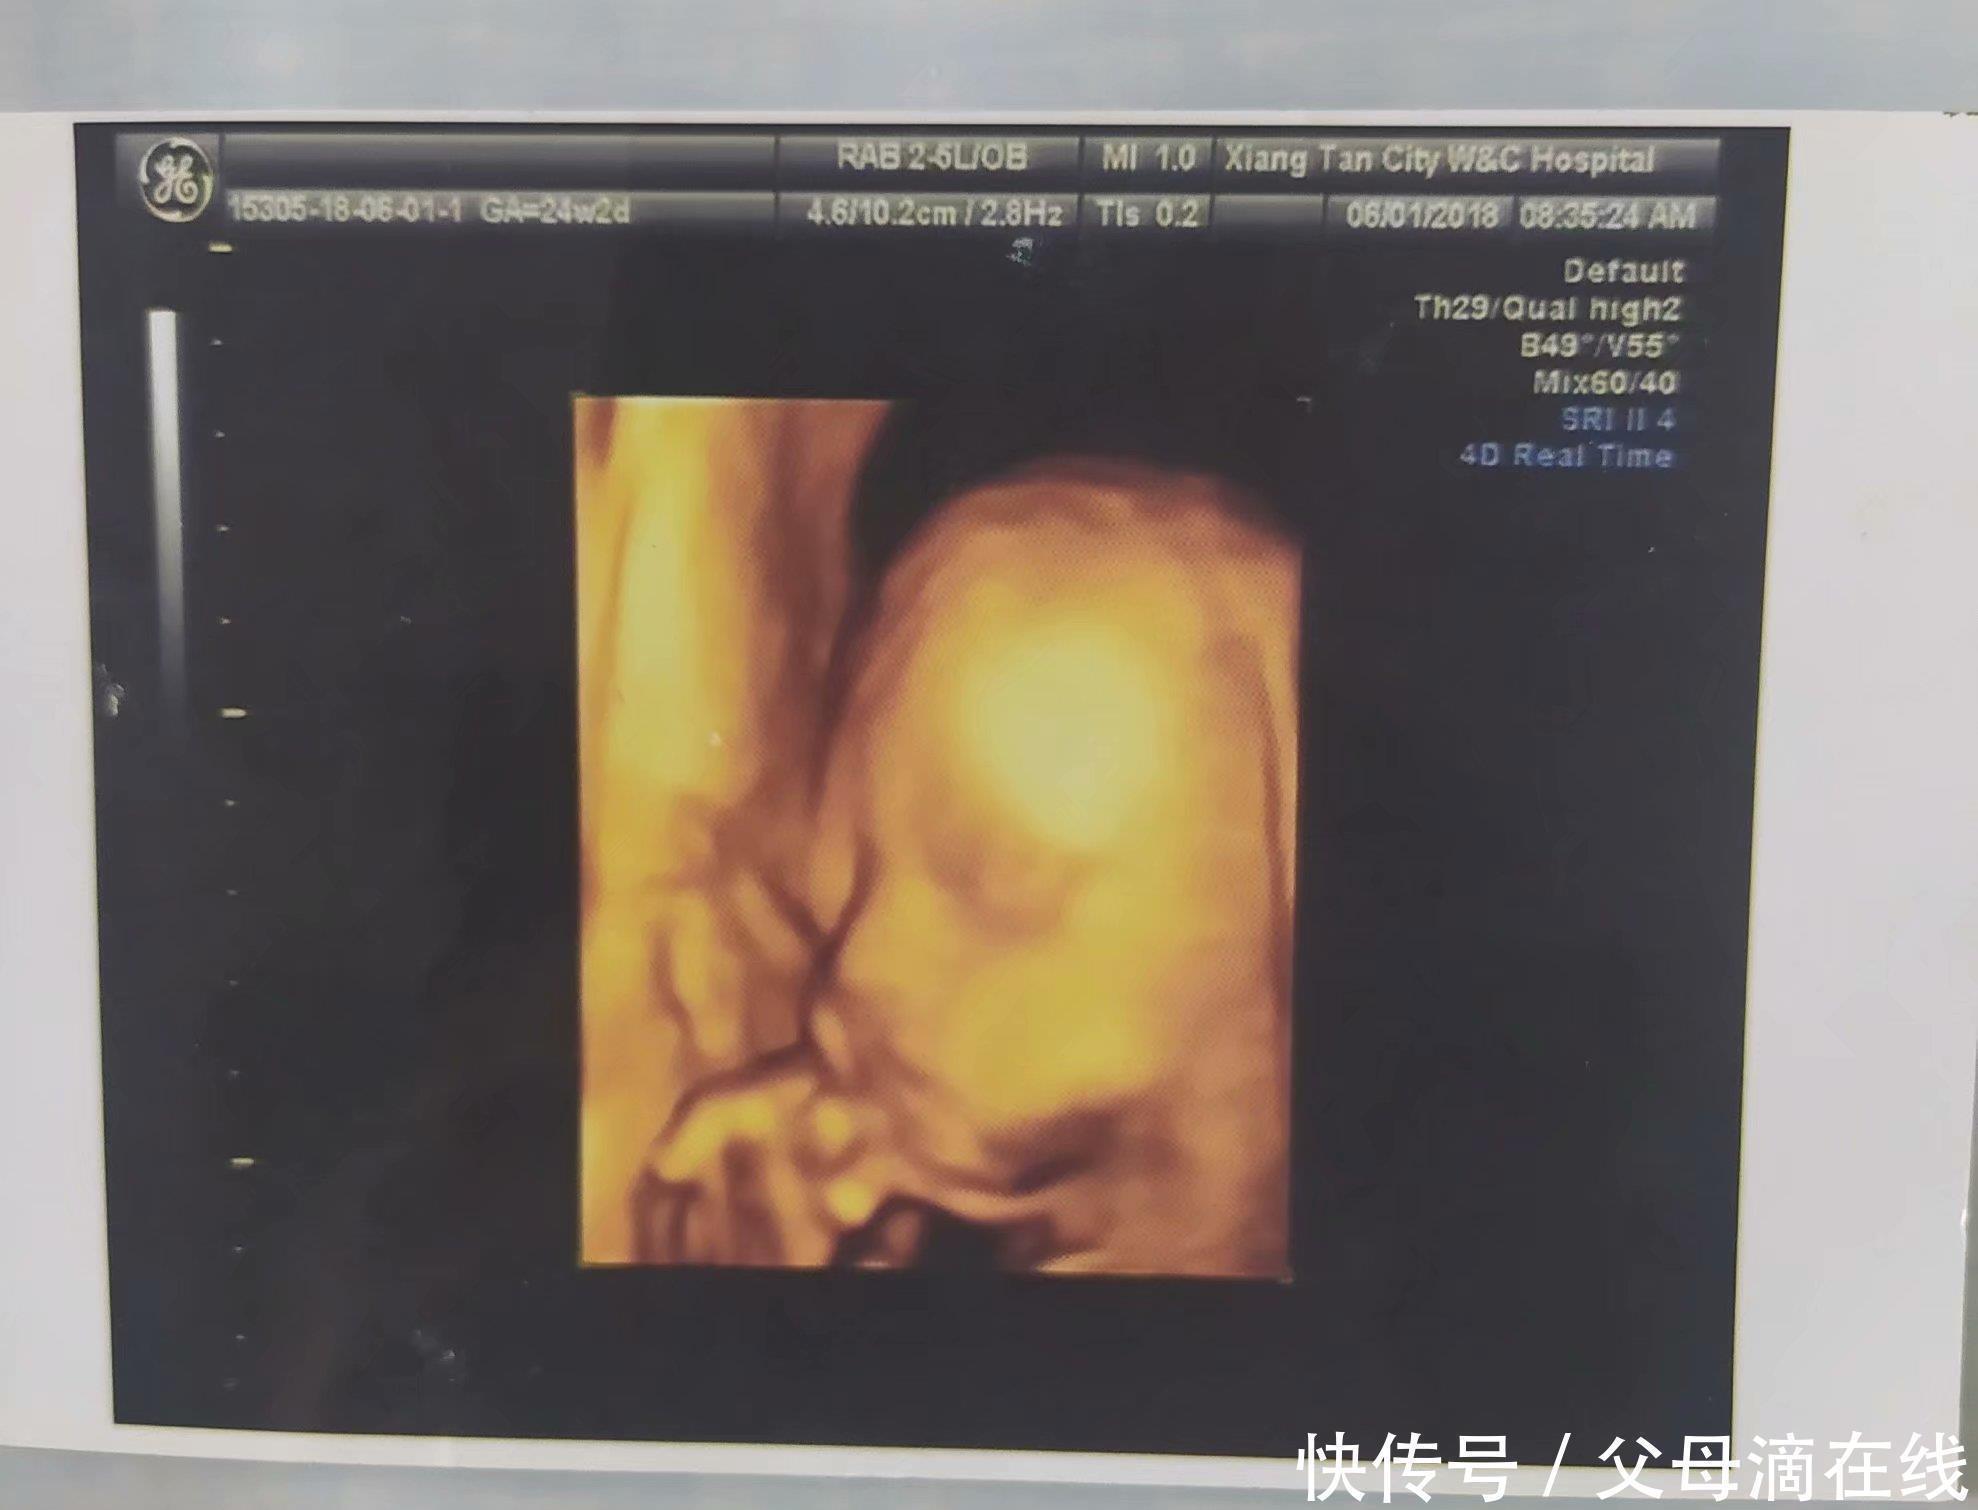

胎动|孕期大排畸检查,快速通过及注意事项,你想知道的都在这里( 二 )

- 四维彩超|孕期最关键的4次产检,就算再忙,宝爸也要陪孕妈一起